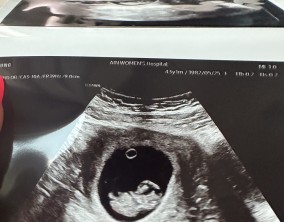

두 줄에서 심장소리까지, 따뜻하게 이어진 시간